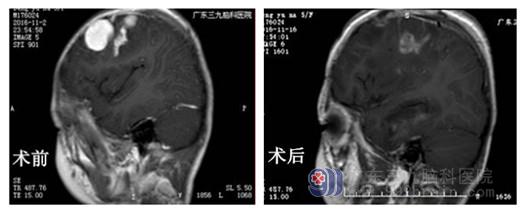

小儿神经外科杨宝应主任检查发现,小钰脑中长的肿瘤大小约5.3cm×2.0cm×2.6cm,不排除为恶性肿瘤,要及时治疗,不然有生命危险。小钰妈妈告诉医生,平时摸小钰的脑袋左侧额部发现有肿块,但也没见她喊头疼,或哪里不舒服,没想到患了肿瘤。目前,小钰已做完肿瘤切除手术。术后病理结果提示:恶性孤立性纤维性肿瘤/间变性血管周细胞瘤(WHO III级)。